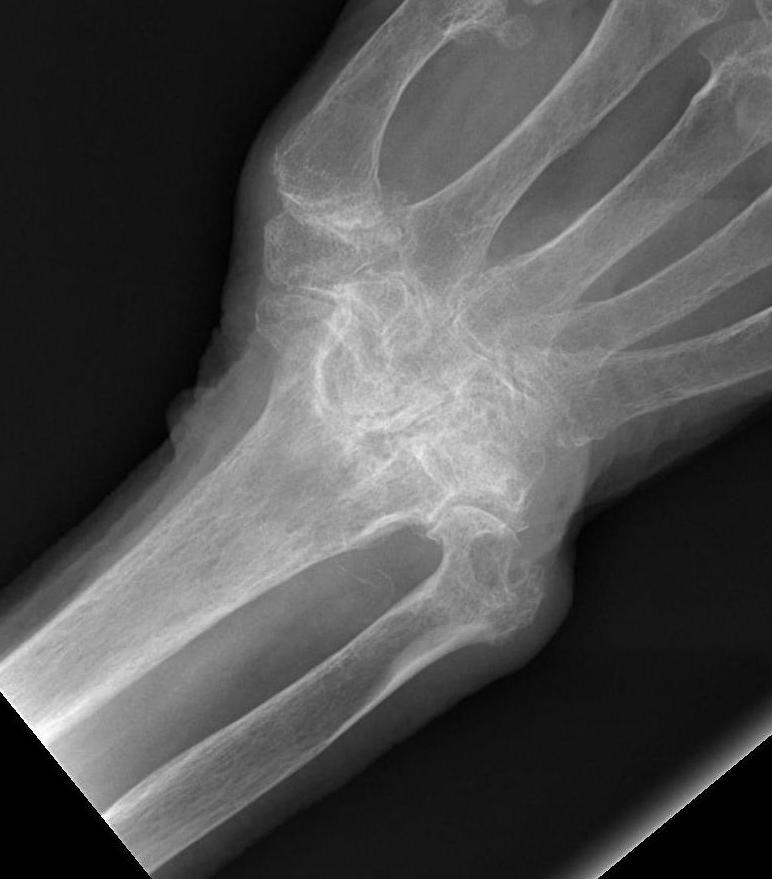

RA wristRA wrist

Wrist RA

Rheumatoid WristRheumatoid Wrist Carpal Collapse